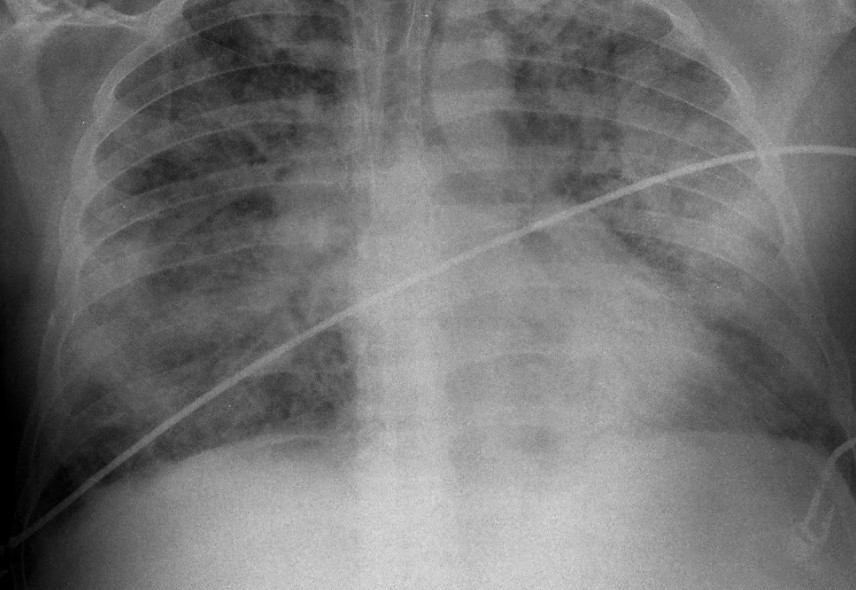

¿Qué es la neumonía?

La neumonía es una infección del pulmón que puede ser causada por diferentes gérmenes como bacterias, virus y hongos. Es la infección que con mayor frecuencia justifica el ingreso de un paciente en el hospital y la causa mas frecuente de muerte de origen infeccioso. Se clasifican según se adquieren en el ámbito extrahospitalario (neumonía […]